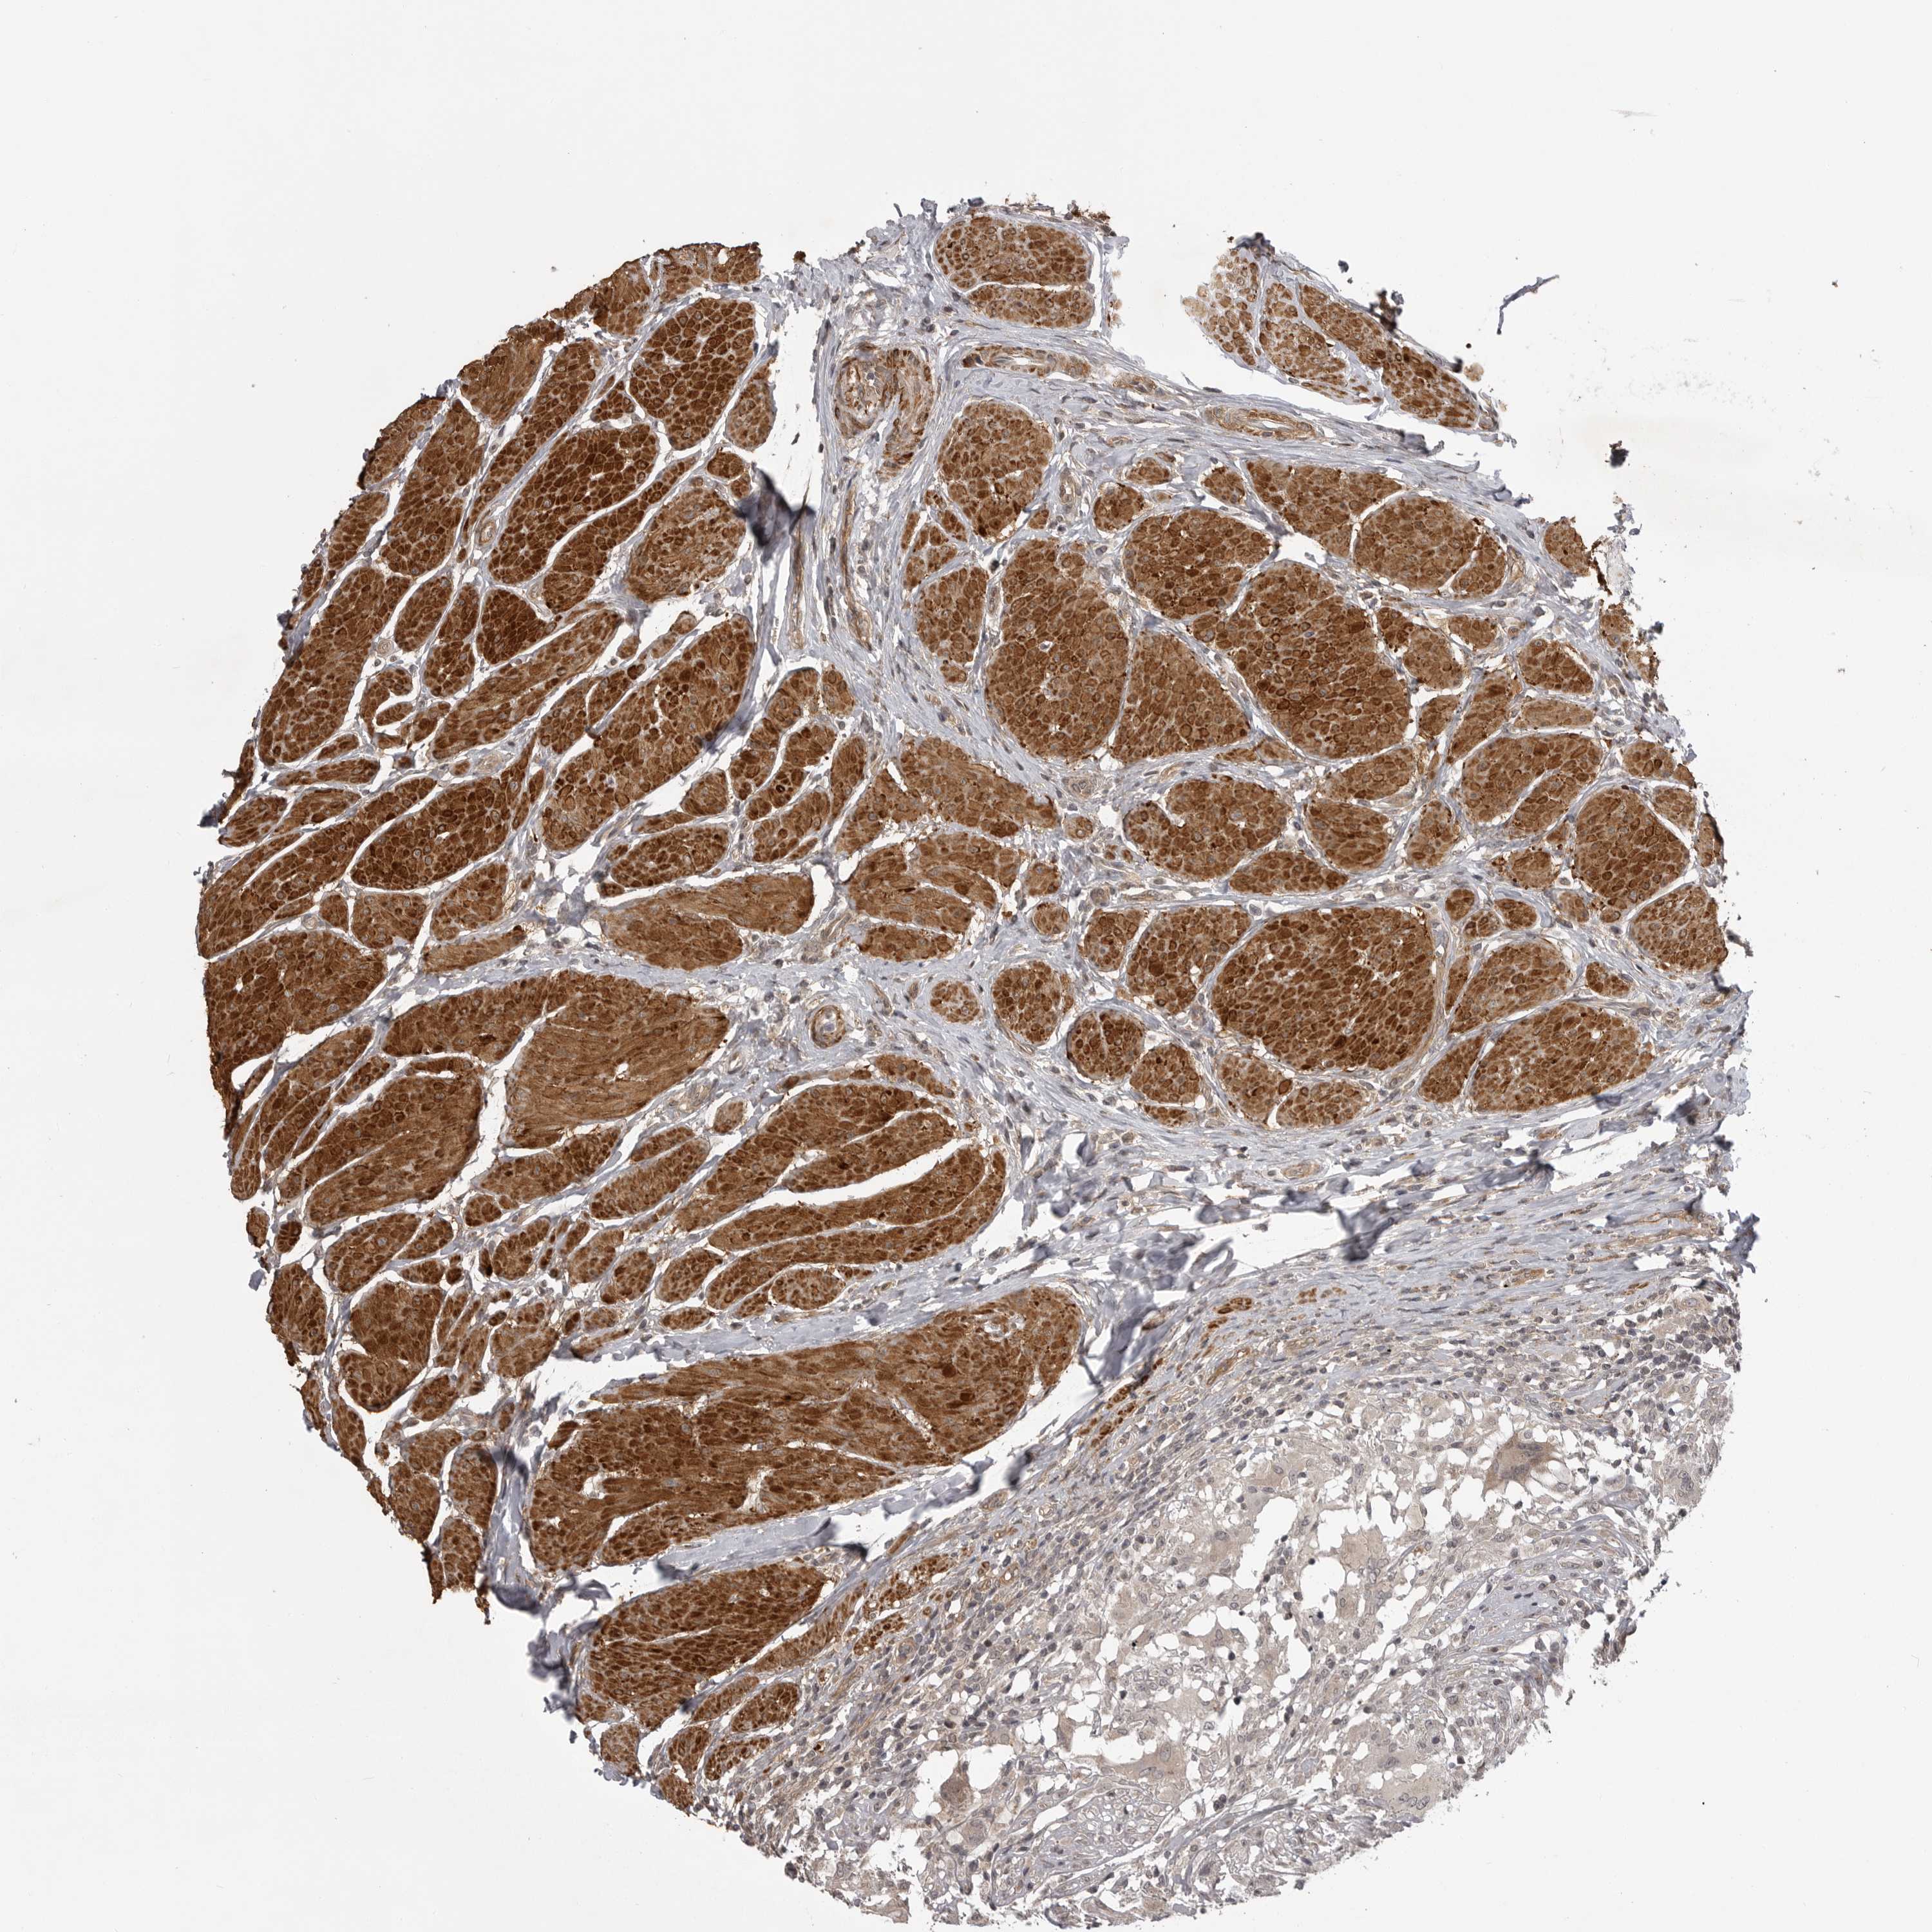

UROTHELIAL CANCER - Protein expressioni

A mouse-over function shows sample information and annotation data. Click on an image to view it in a full screen mode. Samples can be filtered based on level of antibody staining by selecting one or several of the following categories: high, medium, low and not detected. The assay and annotation is described here.

Note that samples used for immunohistochemistry by the Human Protein Atlas do not correspond to samples in the TCGA dataset.

Antibody stainingi

Antibody staining in the annotated cell types in the current human tissue is reported as not detected, low, medium, or high, based on conventional immunohistochemistry profiling in selected tissues. This score is based on the combination of the staining intensity and fraction of stained cells.

Each image is clickable and will lead to virtual microscopy that enables deeper exploration of all samples and also displays staining intensity scores, fraction scores and subcellular localization as well as patient and tissue information for each sample.

Antibody HPA024730

Antibody HPA024731

Antibody HPA024817

Staining

High

Medium

Low

Not detected

Intensity

Strong

Moderate

Weak

Negative

Quantity

>75%

75%-25%

<25%

None

Location

Nuclear

Cytoplasmic/membranous

Cytoplasmic/membranous,nuclear

Urothelial carcinoma, Low grade

Urothelial carcinoma, High grade